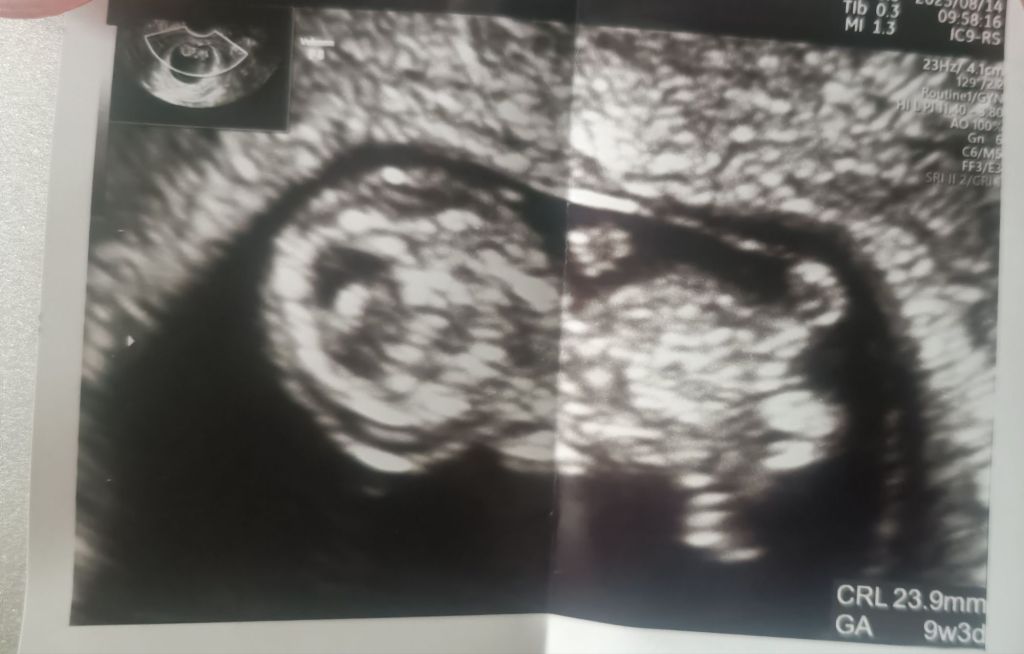

無事2度目も心拍確認できました😭

モニターに映し出された映像からは、前回よりも明らかに人の形に近づいたまめささんの白い影が見えました。

先生が👨⚕️

ここが足で、こっちが手ですね。

大きさも十分ですね。

と、ゆっくり説明してくださいました✨

動いている心臓も見えて、音も聞かせてもらって

診察時のエコー写真がでます